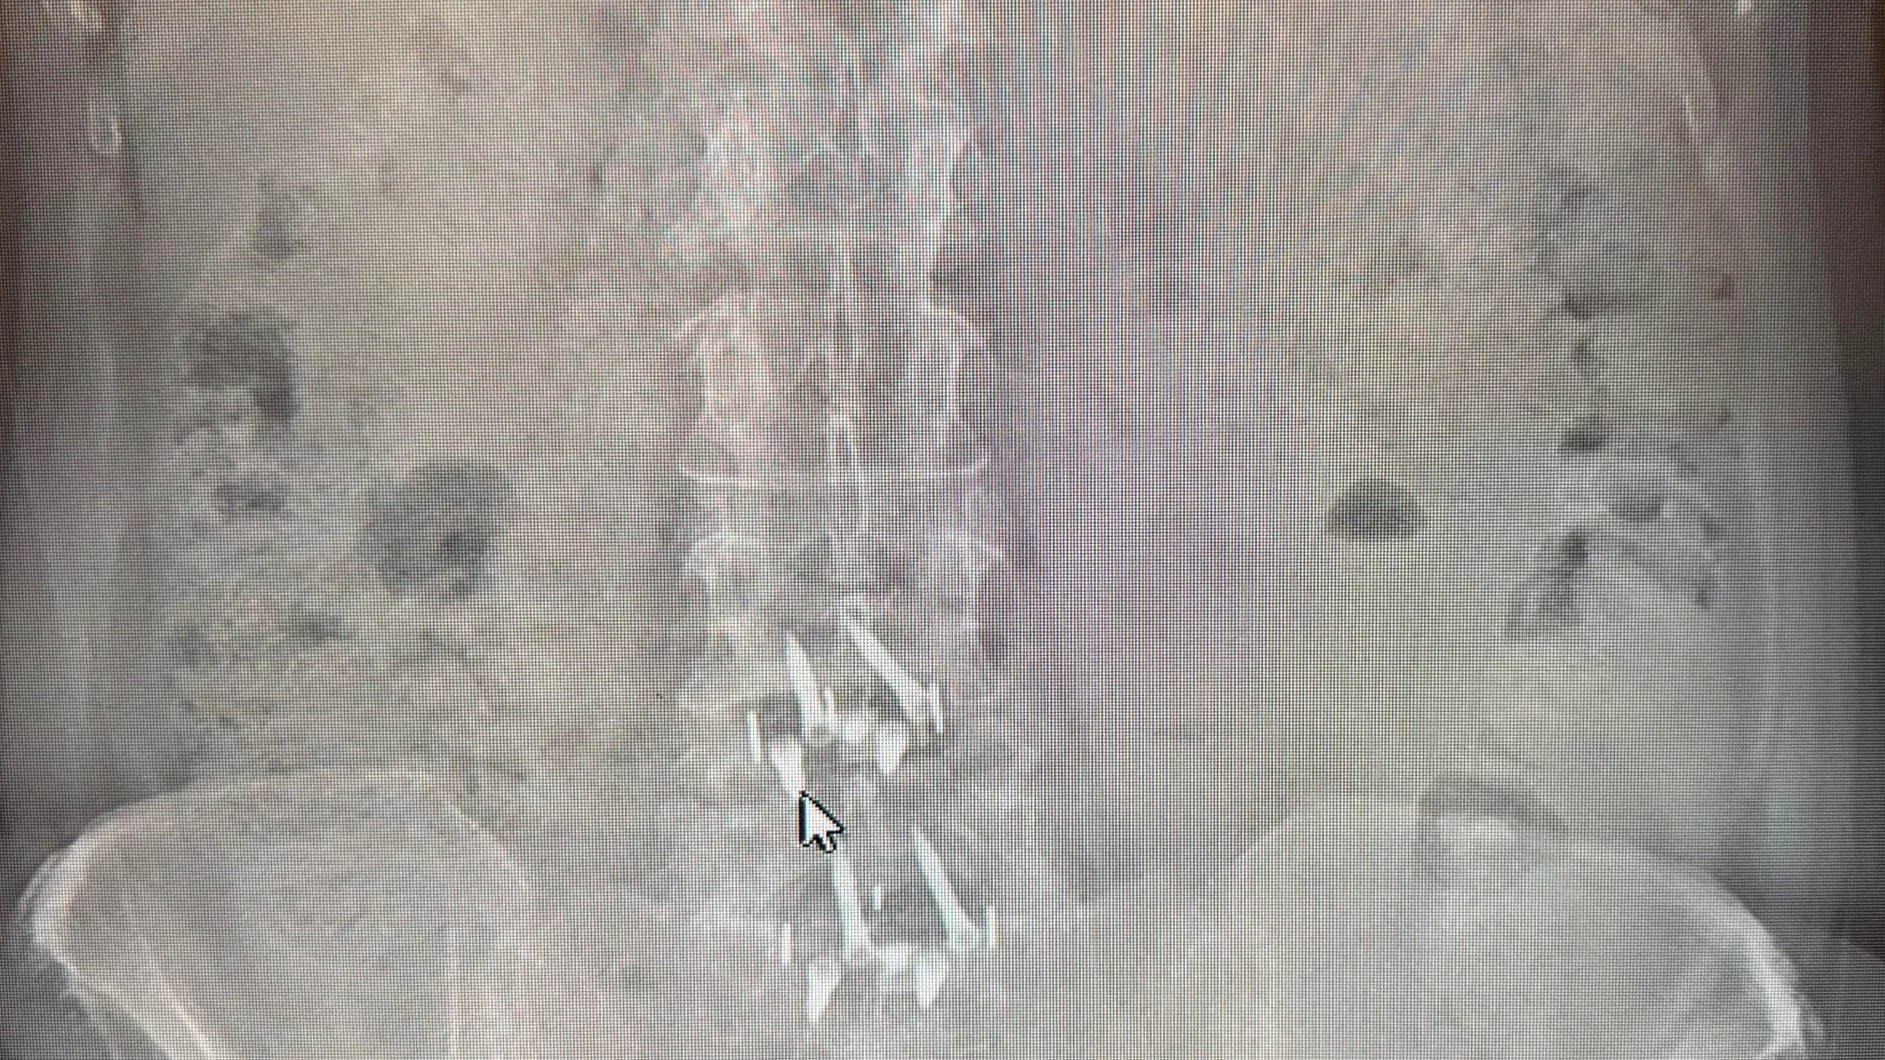

Cindy’s last x-ray shows a slight unevenness in her hip height creating a slight curve in her back. Not sure what she will do about it.